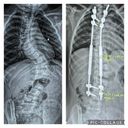

Since, Koledyn has been seen at Essentia Health in Duluth, by Dr.Kathryn Huff and several other pediatric othoropedic specialists. Koledyns spine at this time had a 67 degree curve and a 43 degree curve.

Koledyn will be having MAGEC ( MAGnetic Expansion Control System) rod surgery March 14,2025. The MAGEC system, which includes implantable rods and an external remote control, are used to brace the spine while the child is still growing to minimize the progression of scoliosis.